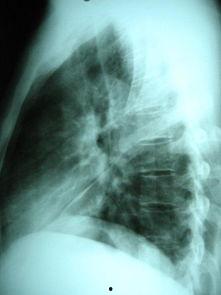

想象你的胸腔里突然来了很多“水”,这些“水”可不是普通的清水,而是胸腔积液。这玩意儿多了可不行,会让人呼吸困难,甚至威胁生命。这时候,医生就会施展他们的魔法——胸腔积液穿刺,把那些该死的“水”抽出来,让胸腔恢复平静。

胸腔积液穿刺,顾名思义,就是医生用一根细长的针,从你的胸腔壁上穿个小洞,把积液抽出来。听起来有点恐怖,但其实,这可是个技术活儿,需要医生有高超的技艺和丰富的经验。